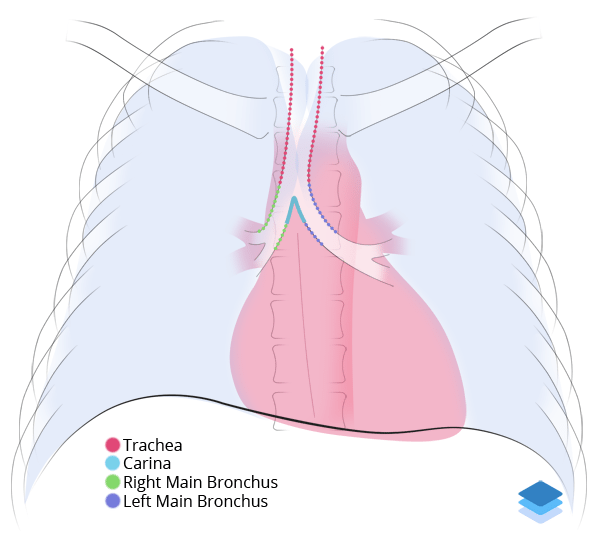

Labelled radiographs and CT/MRI series teaching anatomy with a level of detail appropriate for medical students and junior residents.

Chest

Chest

Chest radiograph & CT anatomy

Chest

Chest

Chest radiograph & CT anatomy